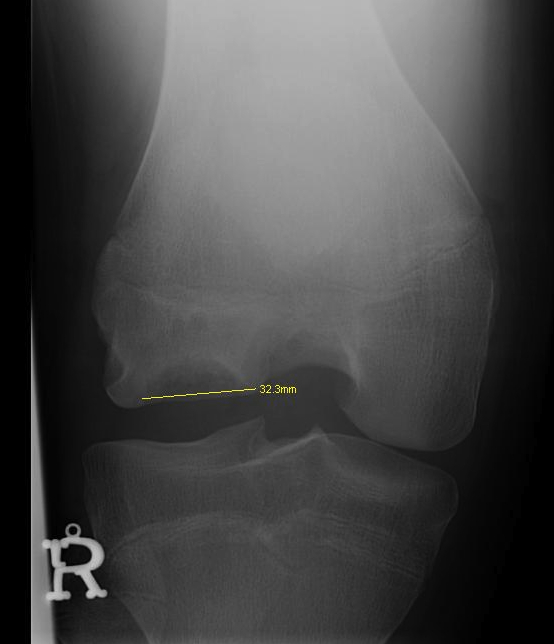

Xray

Intercondylar view / notch / tunnel view imperative

- most commonly seen in this view

- can miss the lesion unless have flexed knee view 30-50o

Location

Medial Femoral Condyle 85%

- lateral aspect of the MFC

- PCL origin

Lateral Femoral Condyle 10%

- most common in the central region of the LFC